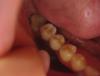

MamAnuta Опубликовано 31 октября, 2013 Поделиться Опубликовано 31 октября, 2013 Доброго времени суток, уважаемые специалисты!Заранее извиняюсь, за качество снимков - домашняя фотосессия завтра попробую запросить их по электронке с клиники. Сама проживаю в другом городе. Год назад мне установили имплантанты на нижней челюсти 2 шт на место 6 и 7 зуба справа (винтовые Ankylos)Коронки поставили только 29 окт (т.к. верхние зубы "провисли" и было принято решение их "повернуть" к центру и "поднять" чтобы не спиливать при установке коронок - это заняло 6 мес).При выборе материала коронок мне предложили либо металлокерамику либо циркониевые. Я выбрала цирконий, т.к. сказали, что получше... эстетичнее что ли... Если честно, я думала, что циркониевые зубы, да и вообще имплантантированные зубы, выглядят как настоящие, только без дефектов... У меня же получился вид своего собственного, но только леченого перелеченого (как будто был кариес во всю полость зуба и закрыт более светлой пломбой), а посередине кругленькие желтенькие пломбочки, закрывающие технологические отверстия.Вид никакой об эстетике вообще молчу - ее там нет... При установке коронок (их сделали две слитные, но в каждой коронке отдельное отверстие для фиксации) я сразу высказала сомнение в цвете жевательной поверхности, т.к. она сильно (на мой взгляд) отличалась от других своих зубов и от боковой поверхности самих коронок.На что врач сказал, что это такие технические нюансы - так изготавливается коронка. Но после консультации в соседнем кабинете с кем-то по телефону сказал, что можно сделать и по-другому, но надо будет доплатить по 12тыс за каждую коронку за изготовление абатментов - вроде так их называл (я не специалист, поэтому могу врать в терминах).И вообще я первый в его практике пациент, который предъявляет претензии к цвету жевательной поверхности зуба - мол все равно ее никому не видно...Я сказала, что раз по-другому сделать технически нельзя, то пусть ставит так как есть.Подгоняли очень долго - все что-то мешало при накусывании. Долго отпиливали то ли сверху зубы, которые полгода выпрямляли, чтобы не пришлось стачивать, то ли снизу зуб за 50 тыс - даже не поняла Вроде все подпили, все хорошо, отфотографировали... дали зеркало...На вопрос почему нельзя было подобрать цвет этой пломбы под цвет поверхности зуба, доктор вспылил и сказал, что не понимает, что мне не нравится, а потом вообще сказал чтобы я приходила в другой день и они все переделают, никакой доплаты не нужно, просто все будет менее надежно и практически выгнал меня из кабинета, не объяснив больше ничего (у него был уже следующий человек по записи). В связи с этим вопрос - как должны выглядеть нормальные коронки в моей ситуации?Действительно я слишком придирчива и это НЕВОЗМОЖНО сделать иначе технически? Тогда почему врач сказал что переделают за свой счет? Что они мне там сделают - уже даже и думать не хочется Просмотрела кучу фото в интернете циркониевых коронок и такого чуда как у меня нигде не нашла На самом деле хочется послушать профессионалов - может я зря на доктора обижаюсь? Но тогда странно, что за все это убожество надо платить ТАКИЕ деньги - 2 зуба обошлись более чем в 100тыс руб...Муж считает, что я придираюсь, хотя у самого год назад вставлено тоже 2 зуба в этой же клинике - на них не видно ничего - просто обычные нормальные зубы. Хочется объективности - прошу Вашей помощи Ссылка на комментарий

MamAnuta Опубликовано 2 ноября, 2013 Автор Поделиться Опубликовано 2 ноября, 2013 это винтовая фиксация коронок. В них действительно есть технологическое отверстие - это их минус. Но есть и плюсы.На абатменте можно сделать цементную фиксацию, там нет технологических отверстий, но есть другие минусы. Истина где-то посередине.http://forum.stom.ru/topic/23130-vintovaia-vs-tcementnaia-fiksatciia-koronok-na-implan/Спасибо большое!Все прочитала, что стало понятнее, что-то совсем не поняла (т.к. не врач) Что касаемо моей ситуации... раз уж сделали винтовую, пусть будет винтовая. Мне на самом деле не принципиально - раз врач решил в моем случае сделать винтовое крепление - ему виднее. Меня больше смущает эстетика, внешний вид моих зубов.Но фото винтовых коронок, что я увидела все-таки сильно отличаются от того, что поставили мне. На снимках, вывешенных врачами, они везде одинаковы по окраске со всех сторон, у меня же получился как ободок моего цвета вокруг светлой жевательной поверхности.До подгонки этого ободка не было, была просто светлая жевательная и моего цвета боковая поверхность. После подгонки образовался ободок, видимо из-за того, что подтачивали саму коронку и стал виден этот наружный слой на срезе.А шахты, выходит, просто безобразно (=некрасиво) и неумело запломбировали Подскажите, возможно ли в моем случае сделать приличную циркониевую коронку, чтобы она не отличалась по внешнему виду от остальных зубов без всяких полосок, ободков и пр. (шахты я уверена можно закрыть так, что их не будет видно) ? Ссылка на комментарий

MamAnuta Опубликовано 2 ноября, 2013 Автор Поделиться Опубликовано 2 ноября, 2013 Вам же предложили переделать... СоглашайтесьДа я и не против Просто мне, идя на следующий прием, надо знать на что я могу рассчитывать и что можно сделать технически, а что нельзя.Поскольку в этом совсем не разбираюсь, многих нюансов не знаю, то меня легко ввести в заблуждение, вот и хочется разобраться, чтобы не быть слепым котенком скорее да, чем нет.то есть то, что сказал мне доктор, что технологически сделать жевательную поверхность одного цвета с боковой невозможно - это неправда? И еще смущает несколько форма зубов - она не слишком ли бочкообразная?? И вообще, уважаемые профессионалы своего дела, не могли бы вы прокомментировать фото коронок, которые мне изготовили, как вы обсуждаете работы друг друга в соответствующей теме. Я просмотрела их - многие просто великолепны и нисколько не отличимы от нормальных зубов - я в большинстве случаев и угадать не могу где и что, а вот то НЕЧТО, что находится сейчас у меня во рту, я даже не знаю как и назвать... порнография какая-то... (прошу прощения за мой французский ) Ссылка на комментарий